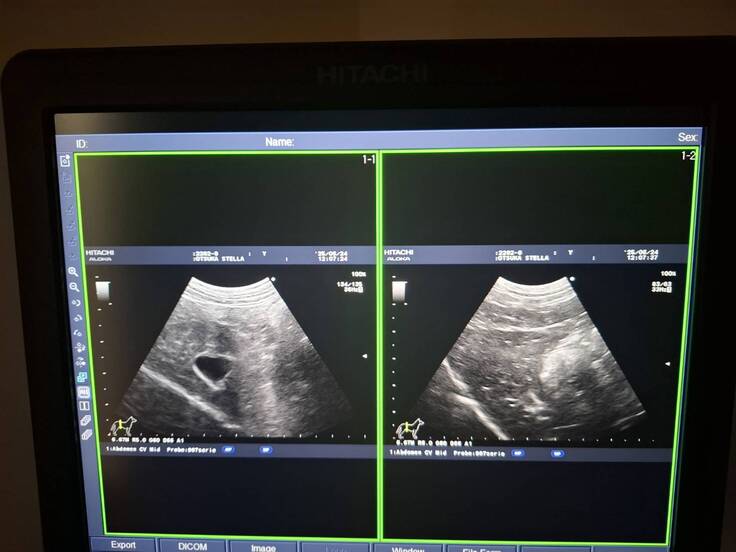

ステラの通院でした。状態が良くないです。

今日はステラの通院でした。。。が、実は血液検査の結果、

アラニンアミノトランスフェラーゼ(肝臓障害など)の数値が1000と出てしまいました。

基準値が22-84なので、相当悪いです。

すぐに入院をしてもいい状態ですが、

本人が元気なので、今日は連れて帰り、数日、様子を見ることとしました。

何かあればすぐに病院へ、

状態が落ち着いていれば1週間肝臓の薬と飲んで様子を見ます。

エコーの状態では悪い様子はなさそうです。

元々肝臓の数値は悪かったものの、

ここまで高いのは初めてなので心配をしています。

考えられるとしたら分子標的薬の副作用も考えられるようです。

ということで、1週間は分子標的薬はストップすることにしました。